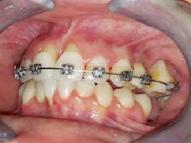

Lâexamen exobuccal Ă©tait sans particularitĂ©s. Lâexamen endobuccal a objectivĂ© une inflammation marginale modĂ©rĂ©e Ă sĂ©vĂšre gĂ©nĂ©ralisĂ©e avec un indice dâOleary Ă 68%, un indice gingival (BoP = Bleeding on Probing) Ă 76%, et un trama occlusal sur 42 (Figure 1). Le bilan parodontal montre des sites avec une profondeur de sondage (PS) de 12mm, et plus de 50% des dents prĂ©sentant une perte dâattache â„ 5mm. Le bilan radiographique a montrĂ© des pertes osseuses terminales, avec un rapport perte osseuse/Ăąge Ă 4,5 (Figure 1)

La thĂ©rapeutique Ă©tiologique a consistĂ© en une Ă©ducation Ă lâhygiĂšne bucco-dentaire, une Ă©limination des facteurs de rĂ©tention de plaque, lâextraction 42+rĂ©section radiculaire et rĂ©alisation dâune contention en fibre de verre avec la couronne ; dâune instrumentation non chirurgicale supra et sous gingivale

par quadrant (3) combinĂ©e Ă une antibiothĂ©rapie (3,4). Une chirurgie avec lambeau dâaccĂšs selon la technique du lambeau avec incision intrasulculaire (open flap) a Ă©tĂ© rĂ©alisĂ©e sur la 46. Une thĂ©rapie parodontale de soutien associĂ©e Ă une phase correctrice a Ă©tĂ© mise en place aprĂšs la thĂ©rapie parodontale active (5). La rĂ©habilitation orale a consistĂ© dans un premier temps Ă rĂ©aliser une correction orthodontique (Figure 2) ; et dans un second temps la conception dâune Ă©pithĂšse gingivale (Figure 3)

AprĂšs 6 mois, pas de profondeurs de poches â„ 6mm, avec un indice de plaque Ă 9% et un indice gingival < 10%. La thĂ©rapeutique non chirurgicale a permis un gain dâattache

stable qui sâest traduit par une diminution des profondeurs de sondage en regard de la 11, 21, et 36 dont le pronostic Ă©tait dĂ©favorable, mais aussi lâapparition dâimportantes rĂ©cessions postthĂ©rapeutique (Figure 4). La chirurgie avec lambeau dâaccĂšs a permis Ă©galement dâamĂ©liorer le niveau osseux de la 46. Le pronostic gĂ©nĂ©ral Ă long terme de la patiente a Ă©tĂ© amĂ©liorĂ©.

La réévaluation Ă 3 mois a montrĂ© une amĂ©lioration de lâĂ©tat parodontal avec plus de 90% de sites prĂ©sentant des PS †4mm (3). LâefficacitĂ© du dĂ©bridement mĂ©canique non chirurgical associĂ© Ă un bon contrĂŽle de plaque individuel dans le traitement des parodontites sĂ©vĂšres a Ă©tĂ© largement documentĂ©e dans plusieurs revues systĂ©matiques (6). Toutefois, la prĂ©sence dâune poche rĂ©siduelle de 6mm avec saignement au sondage sur la 46 reprĂ©sentait un rĂ©sultat incomplet et a nĂ©cessitĂ© dans notre cas un traitement chirurgical par lambeau dâaccĂšs afin dâĂ©viter la progression de la maladie (7).

La rĂ©cession post-thĂ©rapeutique est une observation commune aprĂšs une instrumentation non chirurgicale, particuliĂšrement au niveau des poches profondes et/ou dâun phĂ©notype gingival fin. Notre patiente prĂ©sentait une RT3 sur les incisives centrales rendant son sourire inesthĂ©tique (trou noir). Les restaurations dentaires directes et indirectes et/ou Ă©pithĂšses pouvant ĂȘtre envisagĂ©es (5) ; nous avons optĂ© pour une solution moins invasive en rĂ©alisant une Ă©pithĂšse gingivale. Peu coĂ»teuse et pratique, elle a permis dâoptimiser le rĂ©sultat esthĂ©tique et fonctionnel dans un contexte socio-Ă©conomique limitĂ©.

Figure 4 : (a) Vue clinique Ă 6 mois ; (b) bilan radiographique Ă 3mois (b) ; (c) Retro alvĂ©olaire sur la 46 avant et aprĂšs lambeau dâassainissement